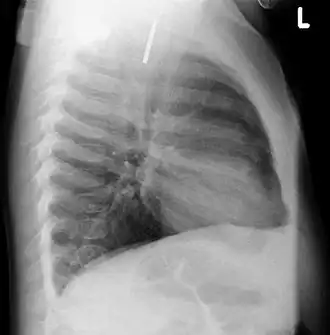

Airways

It is possible for a foreign body to enter the airways and cause choking.[5] A choking case can require the fast usage of basic anti-choking techniques to clear the airway.

In one study, peanuts were the most common obstruction.[6] In addition to peanuts, hot dogs, grapes, and latex balloons are also serious choking hazards in children that can result in death. A latex balloon will conform to the shape of the trachea, blocking the airway and making it difficult to expel with basic anti-choking techniques.[7]